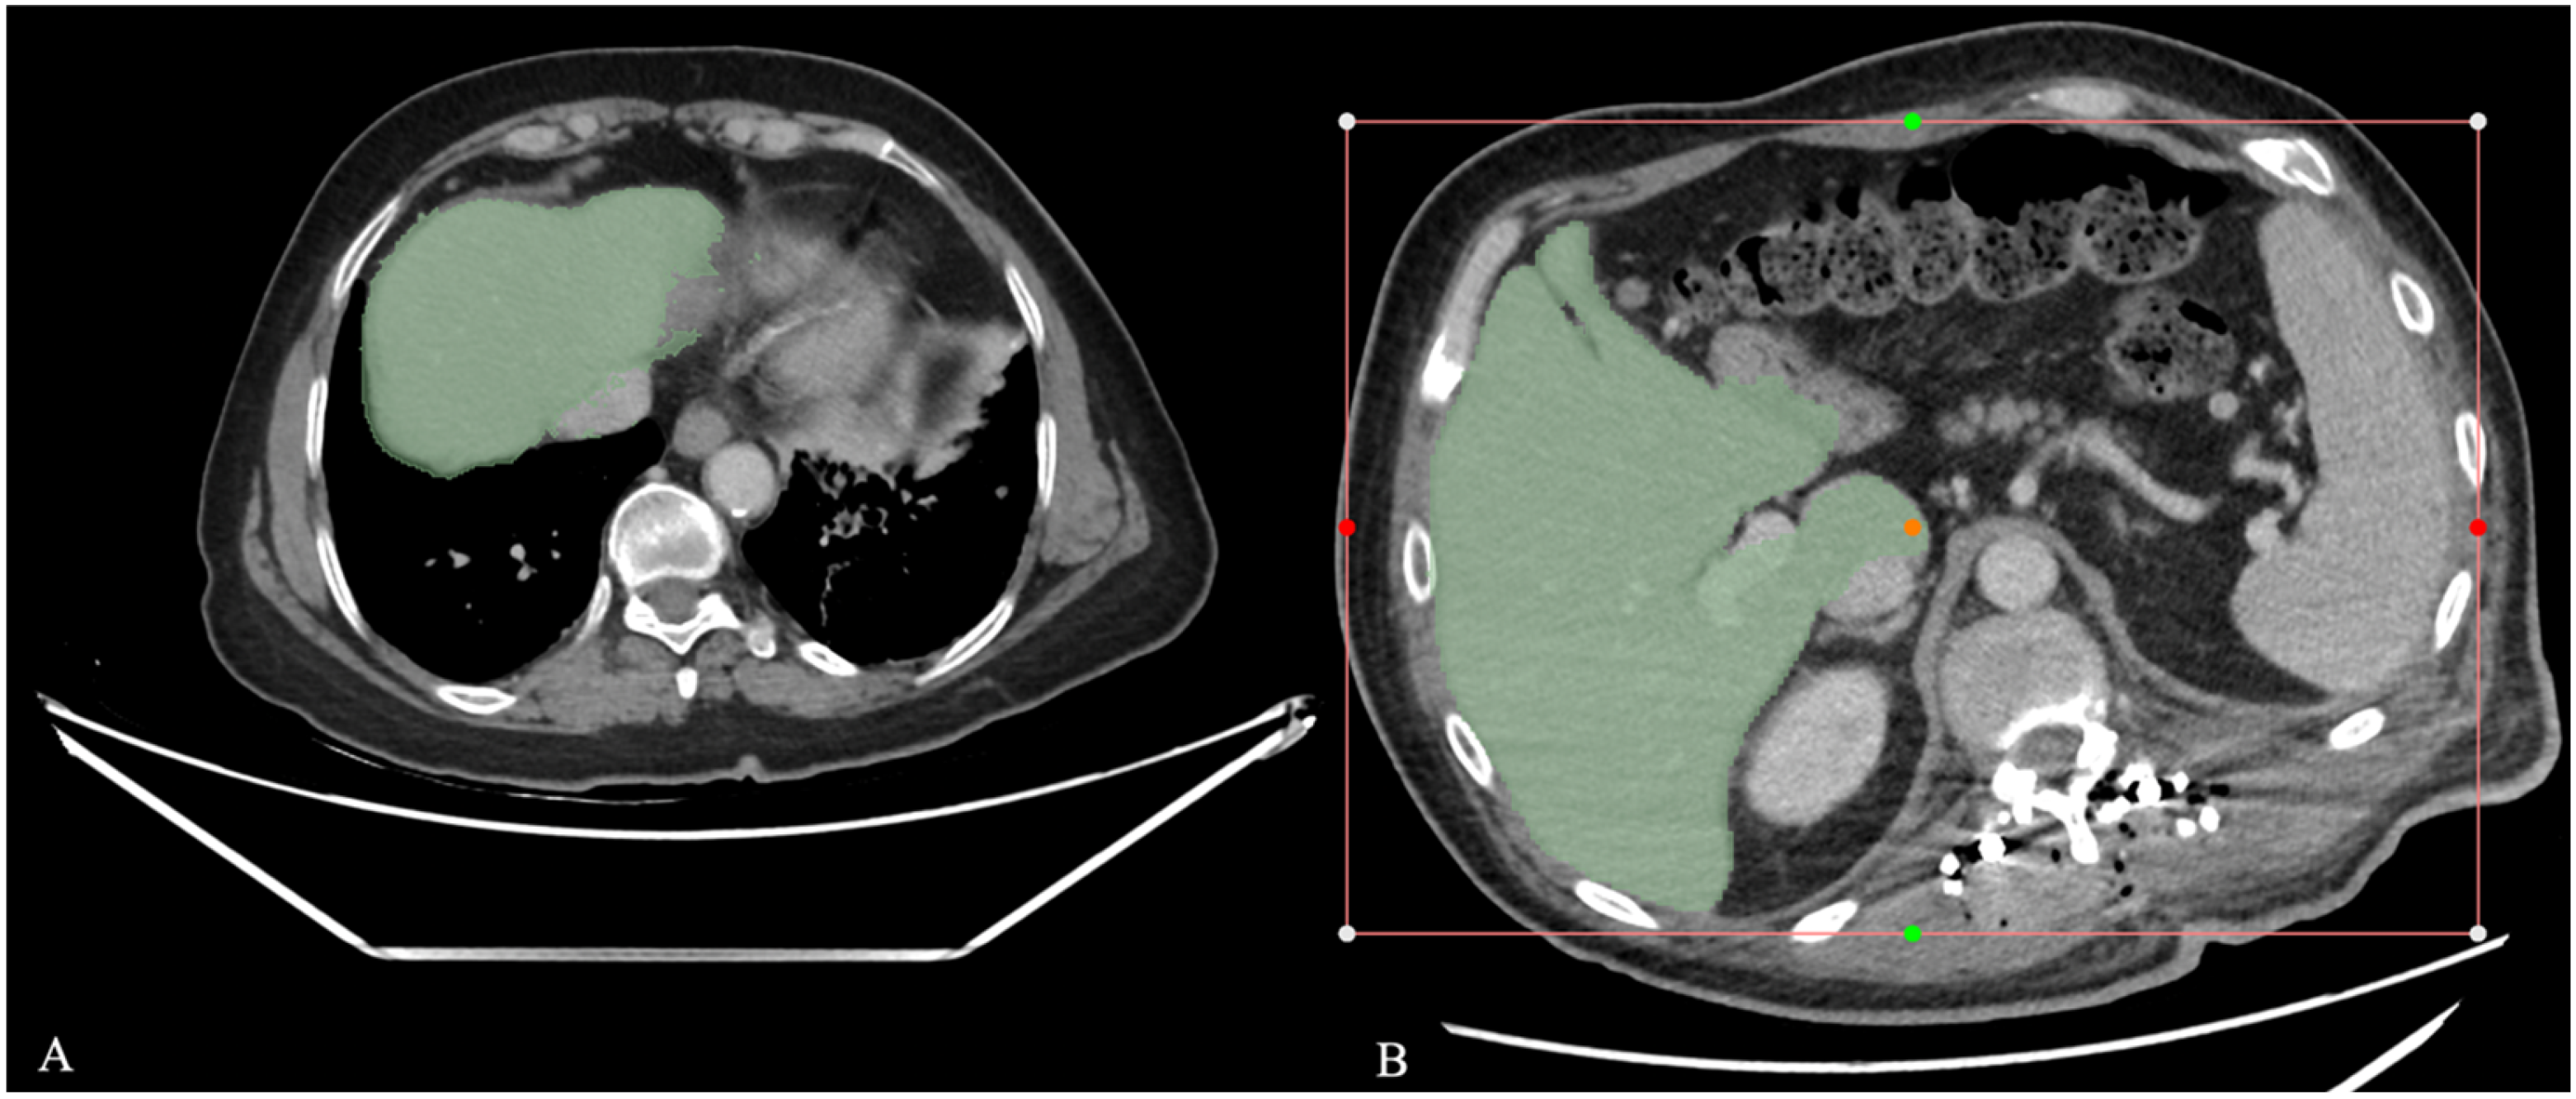

2.3.2. Semi-Automatic Segmentation with the RVX Liver Module

2.3.3. Deep Learning-Based Segmentation with the RVX Liver Module

2.3.4. Automatic Segmentation with the TotalSegmentator Module